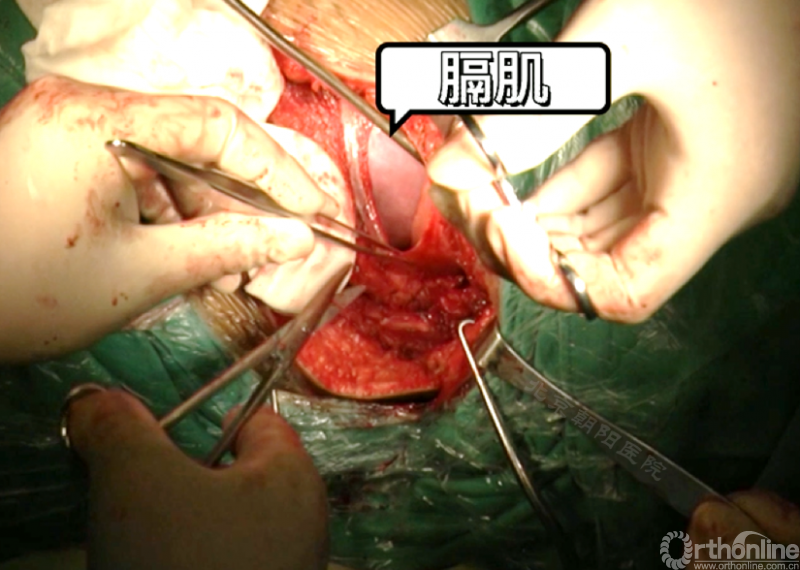

经近端需内固定的椎体(T11)相对应的肋骨表面做一弧形切口,分离浅层软组织直至肋骨表面的多层肌肉组织,切口止于脐的远端偏外侧。

骨膜下环形剥离完整显露肋骨。

切开第11肋骨肋软骨的连接部,并将肋骨靠近脊柱的部位切断。

同理将第12肋骨摘除。

由第12肋前端软骨部位进入腹膜后间隙,可以见腹膜后脂肪。

经腹壁和横膈下方钝性分离腹膜内组织。

切开横膈进入胸腔侧,术中由双肺呼吸改为凹侧单肺呼吸。